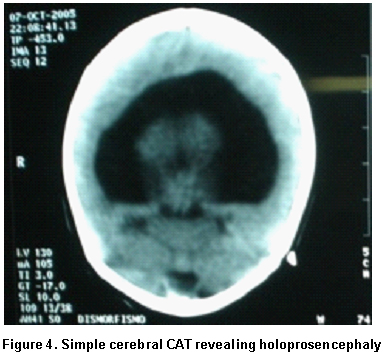

Paraclinical findings. Simple cerebral scan revealed a sole ventricle, fused thalamus, without evidence of structures in the medial line; alobar holoprosencephaly is concluded (Figure 4), echocardiogram: normal, renal ultrasound: normal. Cytogenetic findings (g-banding karyotype, 750-band resolution): 46, XX, of (18)(p11.2) see Figure 5, in the Karyotype the mother was found 46, XX, t (6p, 18p) (18pter’™18p11.2: 6p24’™6qter), der. 18 (Figure 6).